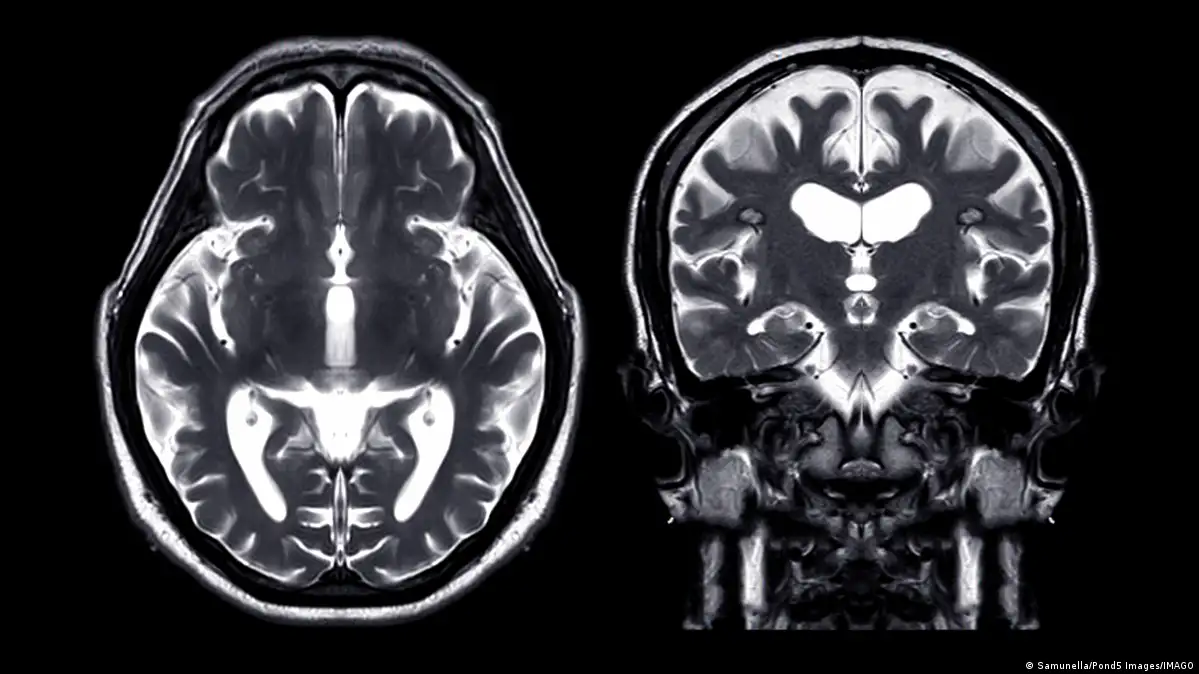

حدوث نزيف في الدماغ، حيث يُحتمل أن يكون النزيف قد ساهم في الخرفصورة من: Samunella/Pond5 Images/IMAGO

وفقًا لموقع "أخبار علوم الأعصاب" (Neuroscience News)، اكتشف العلماء من خلال دراسة بيانات 15 ألف مريض زيادة في حالات الخرف بعد حوالي 5.6 سنوات من حدوث نزيف في الدماغ، حيث يُحتمل أن يكون النزيف قد ساهم في الخرف نتيجة لتراكم مادة بيتا أميلويد أو تلف الأوعية الدموية. بناءً على هذه النتائج، يوصي الباحثون بضرورة إجراء فحوصات عقلية منتظمة للمرضى الذين تعرضوا للنزيف.

قال الدكتور صمويل بروس الباحث الأول في الدراسة، إن النزيف الدماغي يزيد بشكل واضح من خطر الإصابة بالخرف، بغض النظر عن نوعه. وبناءً على ذلك، هذا يعني أن الأشخاص الذين تعرضوا لنزيف دماغي يجب أن يخضعوا لفحوصات منتظمة لفحص وظائفهم الإدراكية، إذ إن ذلك قد يساعد في اتخاذ قرارات بشأن رعايتهم المستقبلية.

من خلال استخدام بيانات التأمين من برنامج ميديكير بين عامي 2008 و2018، درس الدكتور بروس وزملاؤه حالة حوالي 15,000 شخص تعرضوا لأنواع مختلفة من النزيف الدماغي. على الرغم من أن النزيف قد يحدث بسببإصابات في الرأس، إلا أنهم ركزوا على الحالات التي تحدث بشكل عفوي.

وقد وجدوا أن هؤلاء المرضى كانوا أكثر عرضة للإصابة بالخرف بعد حوالي 5.6 سنوات من النزيف مقارنة بأكثر من مليوني شخص لم يتعرضوا لنزيف.

وفقًا لدراسة أجراها باحثو جامعة ويل كورنيل، شملت مجموعة كبيرة من كبار السن في الولايات المتحدة، تبين أن النزيف داخل الجمجمة يضاعف خطر الإصابة بالخرف. وقد لوحظ هذا الخطر بشكل مستمر عبر مختلف أنواع النزيف داخل الجمجمة.